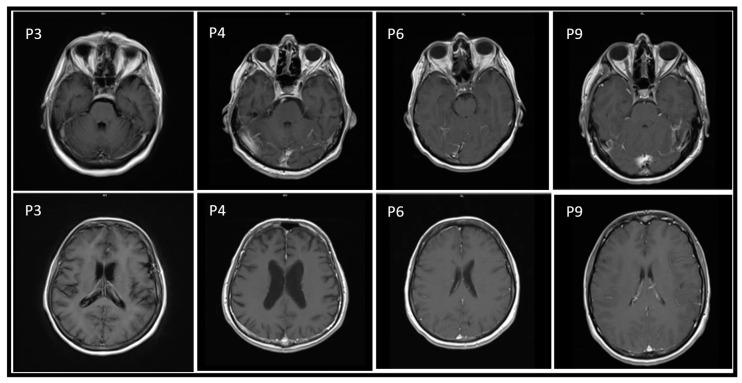

West Nile virus (WNV) infection is a reemerging zoonosis recently provoking significant outbreaks throughout Europe. During the summer of 2018, the number of WNV infections rose with a peak of new diagnoses of West Nile neuro-invasive disease (WNND). Most of the Italian cases were clustered in the Po River Valley. We present a case series of nine patients with WNV infection admitted to the Cardinal Massaia Hospital from 30 August 2018 to 1 October 2018. Demographic, immunovirological, clinical and therapeutic data are shown, and a report on clinical sequelae from the subsequent follow-up in patients with WNV and WNND. We showed the clinical, radiological and biochemical characteristics of WNV-infected patients. The risk factors and the clinical presentation of WNV in most patients in our case series were typical of that described in the literature, although, despite the high morbidity and mortality of WNND, we showed survival of 100% and long-term sequelae in only three patients. Environmental conditions may be essential in WNV outbreaks, and WNND can be clinically neurological multiform. Our long-lasting follow-up with clinical or radiological monitoring confirmed the morbidity of long-term neurological sequelae after WNND. Further studies are needed to investigate the epidemiology and physiopathology of bacterial superinfections after WNV infection.

西尼罗河病毒(WNV)感染是一种再度出现的人畜共患病,最近在整个欧洲引发了重大疫情。在2018年夏季,WNV感染病例数上升,西尼罗河神经侵袭性疾病(WNND)新诊断病例达到峰值。大多数意大利病例集中在波河流域。我们呈现了一个病例系列,包括2018年8月30日至10月1日入住红衣主教马萨亚医院的9例WNV感染患者。展示了人口统计学、免疫病毒学、临床和治疗数据,并报告了WNV和WNND患者后续随访的临床后遗症情况。我们展示了WNV感染患者的临床、放射学和生化特征。尽管WNND发病率和死亡率很高,但在我们的病例系列中,大多数患者的WNV危险因素和临床表现与文献中描述的典型情况相符,不过我们的患者100%存活,只有3例出现长期后遗症。环境条件可能在WNV疫情中至关重要,且WNND在临床上可能呈现多种神经症状。我们通过临床或放射学监测进行的长期随访证实了WNND后长期神经后遗症的发病率。需要进一步研究来调查WNV感染后细菌二重感染的流行病学和病理生理学。